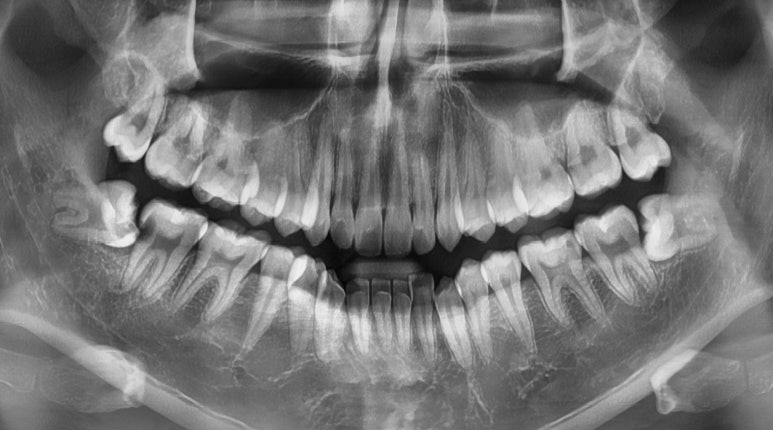

임플란트 수술 전

20대 남성

2023-07-21

가장 최근에 내원하신 20대 초반의 남성분인데요.

내원 2주 전부터 오른쪽 아래 치아에 통증이 있어서 임플란트 상담을 위해 찾아오셨습니다.

엑스레이 보시면 오른쪽 아래(사진상 왼쪽) 사랑니와 #47 치아가 맞닿아있는 부분이 까맣게 보이시죠?

어금니 맨 뒤는 칫솔이 잘 닿지 않는데다가 매복사랑니까지 맹출하면서 #47 치아를 밀어내고,

결국 치아가 썩어 발치 후 임플란트를 하셔야 하는 케이스였습니다.